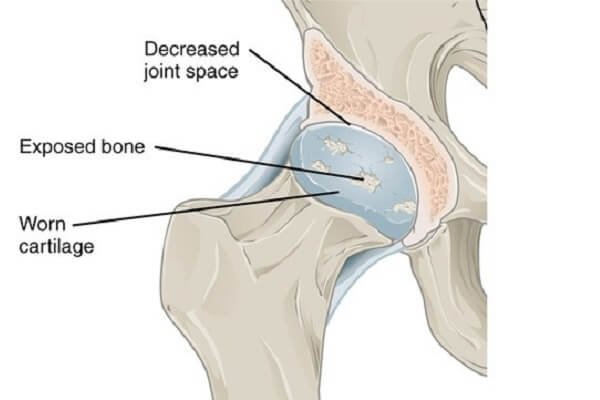

آرتروز و غضروف

غضروف یک ماده سخت و کائوچو مانند بوده که انعطاف پذیر و نرمتر از استخوان است. وظیفه آن این است که از انتهای استخوان ها در مفصل محافظت کرده و به آنها اجازه می دهد تا به راحتی در کنار یکدیگر حرکت کنند.

هنگامی که غضروف آسیب می بیند سطح استخوان ساییده شده و ناهموار می شود و منجر به ایجاد درد در مفصل و تحریک بافت های اطراف آن می شود. غضروف آسیب دیده نمی تواند خود را ترمیم کند زیرا هیچ رگی در غضروف وجود ندارد.

وقتی که غضروف به طور کامل از بین برود، حائل پوشاننده ای که برای استخوان ها فراهم می کند، نابود شده و استخوان ها در مفصل به هم ساییده می شوند که می تواند درد شدید و سایر علائم مرتبط با آرتروز را ایجاد کند.